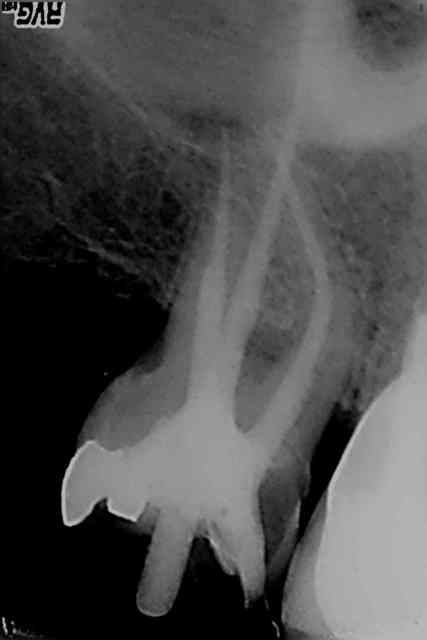

R23 qq9nvn - Eugenol

R30 tnef0w - Eugenol

R31 rguuok - Eugenol

R32 osoz98 - Eugenol